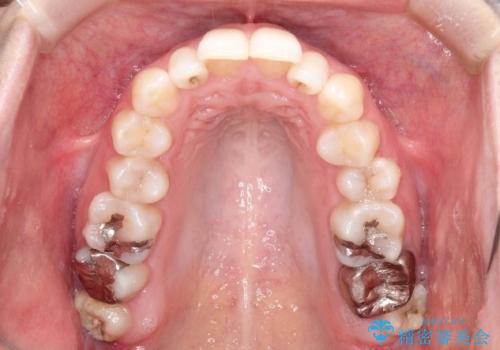

初診時の歯並びの状態としては、上下ともに前歯部の中等度のがたつきがあり、特に左上の前歯が1本内側に入り込んでしまっている状態でした。

また、2mm程度の正中離開がありました。

抜歯なし/インビザラインによるマウスピース矯正にて治療を行いました。

内側に入り込んでしまっている歯を出してくることに非常に時間がかかりましたが、一度歯を歯茎の方へ押し込みそして前へ出してくる2段階の治療を行いました。